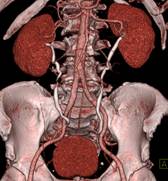

标准规定的临床影像技术检查项目,在脑血管疾病、心血管疾病、系统肿瘤、五官科疾病诊断方面形成特色。科室目前拥有西门子炫速双源螺旋CT,东芝320排螺旋CT及西门子64层螺旋CT,其中东芝320排螺旋CT、西门子双源CT均拥有更快的扫描速度,更高的图像质量和分辨率,更强大的后处理工作站,更广泛的临床应用领域,更低的放射剂量,在呼吸、骨骼、胃肠、神经、心血管等专科领域应用广泛。科室承担多项省部级科研基金资助项目,常年承担西安交大法医系、延安大学影像专业、西安医学院学生及基层医生实习和进修的带教任务,与省内部分地区开展了远程会诊业务,赢得了较高的社会声誉。

320排螺旋CT具备16cm宽覆盖探测器,实现动态容积扫描,360度的各向同性采集能力及[email protected]%密度分辨率的量子探测器,一次心跳全心脏采集,一圈扫描器官成像,一次检查完成多重任务,实现真正的动态容积体灌注及心脏、神经一站式检查;西门子Flash炫速CT扫描系统,具备两套同时旋转的X射线球管及探测器,实现了43cm/s的极快CT扫描速度和75 ms的时间分辨率,完成全胸扫描仅需0.6秒,使得患者做心脏扫描时无须食用β-受体阻滞药,亦无须屏气,并可实现低于1mSv的超低辐射剂量,配置第二代双能量、宽151级纯化能谱,组织鉴别能力进一步提高,可开展多达10余种双能量成像应用。

※肝脏、胰腺、肾脏CT-DSA 及灌注功能一站式检查